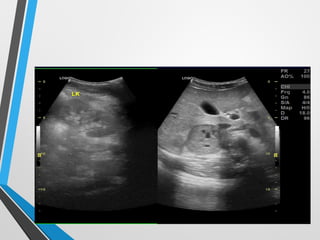

Ultrasound exam..

• A well outlined solid hypoechoic mass lesion with

few tiny cystic degeneration in right suprarenal region

• Mass measuring about 3.5x 5.0 cm

• Two small about 1x1.25 cm hypoechoic lesion is noted at

renal hilum displacing right renal vein

• Ill defined hypoechoic mass like lesion left anterior

paranephric region

• No dilatation of pelvicalyceal system on any side

Ultrasound exam.. • Awell outlined solid hypoechoic mass lesion with few tiny cystic degeneration in right suprarenal region • Mass measuring about 3.5x 5.0 cm • Two small about 1x1.25 cm hypoechoic lesion is noted at renal hilum displacing right renal vein • Ill defined hypoechoic mass like lesion left anterior paranephric region • No dilatation of pelvicalyceal system on any side

well outlined solidhypoechoic right suprarenal mass lesion

Two small hypoechoicmass lesion at right renal hilum displacing RRV